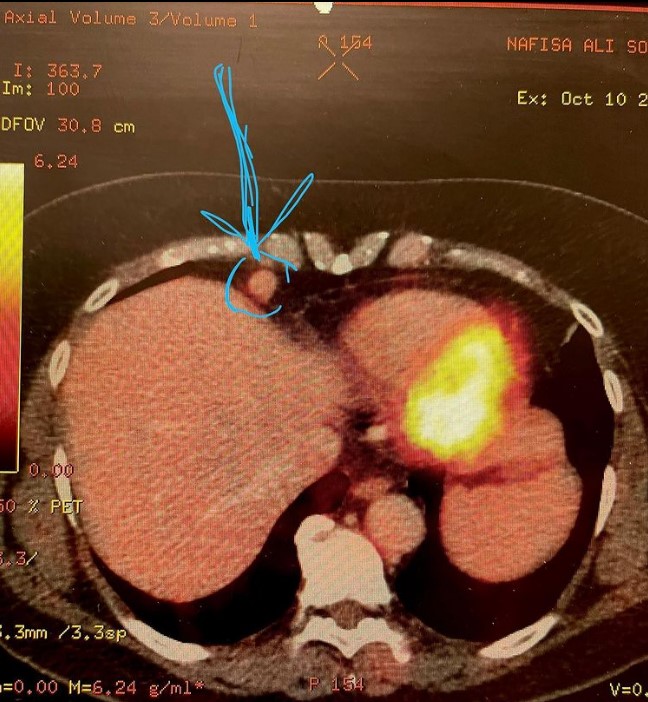

नई दिल्ली, जेएनएन। Actress Nafisa Ali To Undergo Surgery: 'यमला पगला दीवाना' 'लाइफ इन मेट्रो' जैसी बेहतरीन फिल्में करने वालीं एक्ट्रेस नफीसा अली सोढ़ी इन दिनों खतरनाक बीमारी से जूझ रही हैं। उन्होंने हाल ही में सोशल मीडिया पर जानकारी दी है कि फेफड़ों से संबंधित कुछ परेशानी के लिए उनकी सर्जरी कराई जानी है। एक्ट्रेस नफीसा अली ने शॉकिंग खुलासा करते हुए बताया कि फेफड़ों के पास गांठ पाए जाने के बाद उनकी सर्जरी की जाएगी। उन्होंने पीईटी (पॉजिट्रान एमिशन टोमोग्राफी) की एक तस्वीर शेयर करते हुए यह खुलासा किया है। इस खुलासे के बाद उनकी फोटो के कमेंट सेक्शन में वेल विशेज की बाढ़ सी आ गई है।

नफीसा अली ने पीईटी परिणामों की फोटो शेयर करते हुए लिखा, 'मेरा पीईटी किया और उन्होंने (डॉक्टर्स) ने मेरे फेफड़ों के पास एक नॉड्यूल खोजा है। लेकिन यह मेरे पसली के नीचे और डायाफ्राम के ऊपर है। इसलिए इसे हटाने और कैंसर की जांच करने के लिए दाहिनी पसली के माध्यम से एक लेप्रोस्कोपिक सर्जरी करनी पड़ती है। यह सर्जरी शुक्रवार को दिल्ली में होगी।'